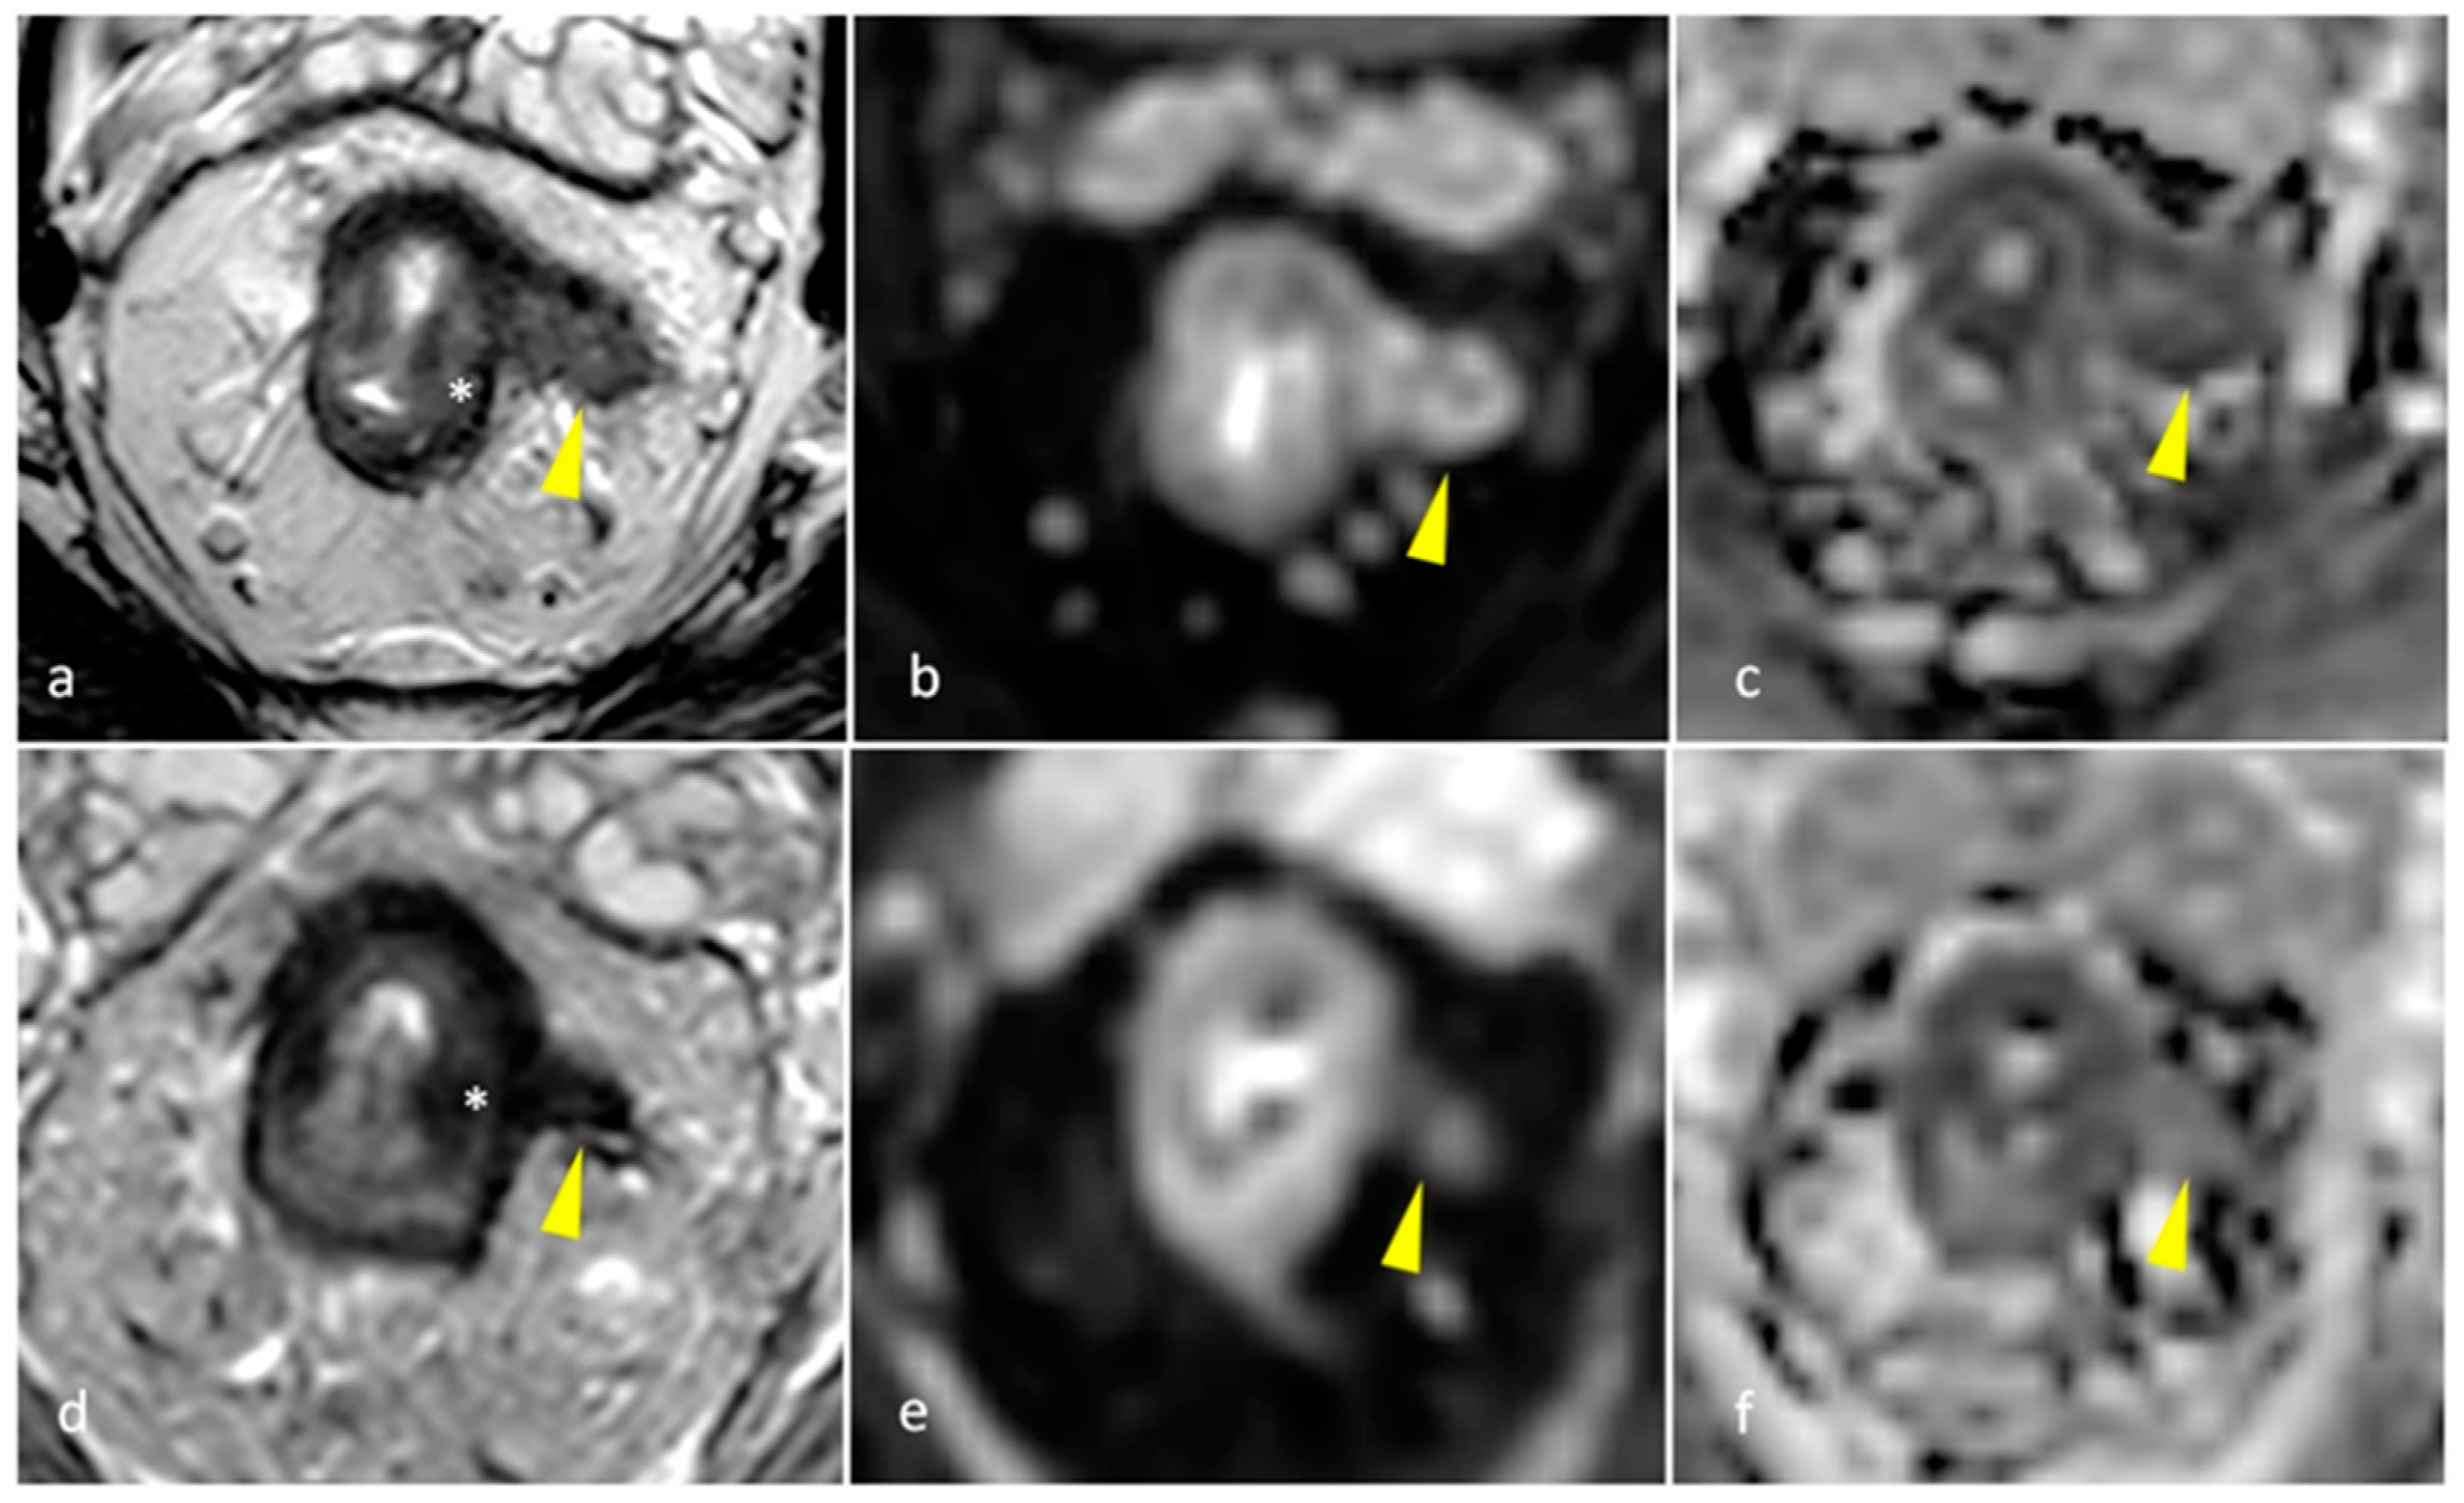

| mrTRG | 1 | Complete Radiologic Response (i.e., no evidence of tumor) |

| 2 | Good Response (i.e., dense >75% fibrosis with no obvious residual tumor) | |

| 3 | Moderate Response (i.e., >50% fibrosis or mucin with a minority of visible tumor) | |

| 4 | Slight Regression (i.e., <50% fibrosis or mucin with a majority of visible tumor) | |

| 5 | No post-treatment changes | |